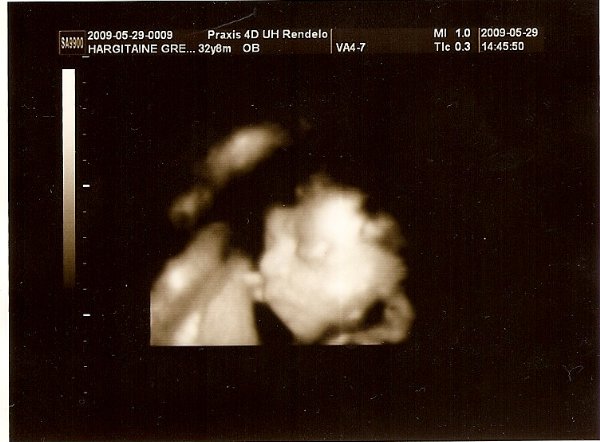

[quote="vicger"][ írta:vicgerimg]https://www.babanet.hu/tarsalgo/attachments/1243880636.351.jpg[/img]

Annyira jó ez a kép szerintem!!!